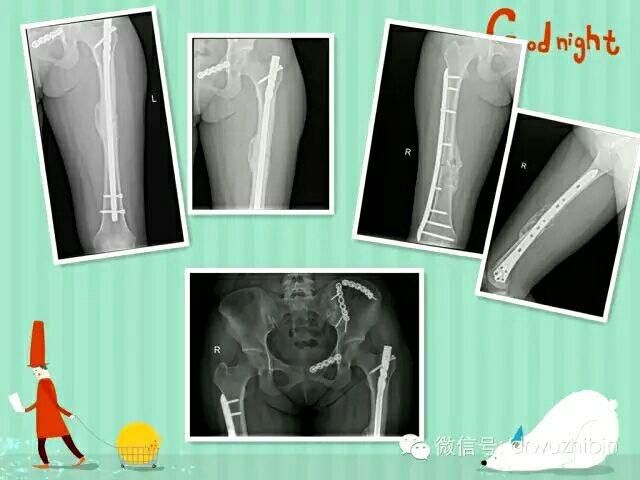

康美醫院充分發揮整個外科團隊的協調作用,按照保命-保肢-保關節-保功能的治療原則,準确評估病情,制定合理治療方案,遵循“微創-康複”的治療理念,搶救了一批多發性創傷患者,積累了豐富的經驗。

以下是近期收治的一名骨盆多發性骨折合并泌尿系損傷、雙側股骨幹骨折的患者,術後康複良好。

更加規範的搶救流程,更加合理使用各種治療器械,更好的療效,是我們追求和努力的目标!